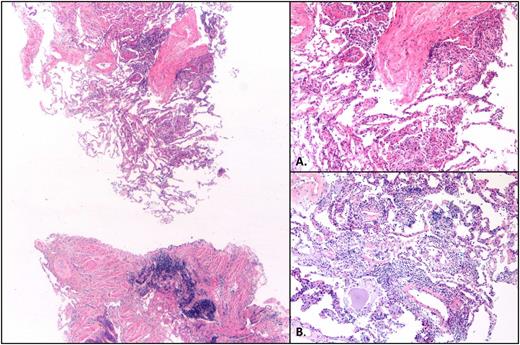

Hematoxylin and eosin–stained sections reveal patchy lung parenchymal involvement by intra-alveolar loose fibrous plugs, intra-alveolar fibrin, reactive pneumocytes, and mild chronic interstitial inflammation (×2.5). (A) Higher magnification (×10) of loose fibrous plugs in alveolar spaces and indistinct granuloma. (B) Higher magnification (×10) of focus with chronic interstitial inflammation.

The first case describes a 71-year-old woman with del(17p) del(11q)-positive relapsed CLL who was treated with ibrutinib at 420 mg daily 9 years after initial diagnosis. Prior therapy included fludarabine and rituximab. One month following ibrutinib initiation, she was hospitalized with dyspnea and hypoxia. Infectious workup was negative. A computerized tomography (CT) scan of the chest revealed widespread interstitial ground glass opacities not noted on CT imaging obtained 4 weeks prior to ibrutinib exposure (Figure 1A-B). Transbronchial biopsy and cytology revealed fragments of alveolated lung parenchyma with chronic interstitial inflammation and organization associated with loosely formed nonnecrotizing granulomas without evidence of viral infection or malignancy (Figure 2). Prednisone, at 40 mg daily, was initiated. The patient improved within 1 week, and ibrutinib was resumed at 420 mg daily on discharge. Three months following discharge, a CT scan of the chest demonstrated resolution of ground glass opacities (Figure 1C). Ten months following her initial hospitalization, the patient presented with dyspnea and increased sputum production without fever. An infectious workup was negative. A CT scan of the chest revealed centrilobular emphysema and superimposed peripheral reticular interstitial lung disease consistent with pulmonary fibrosis. Ibrutinib was held, and prednisone, 30 mg daily, was initiated. The patient improved and was discharged on steroids; ibrutinib was permanently discontinued.